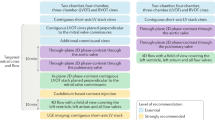

Although echocardiography remains the mainstay imaging technique for the evaluation of patients with valvular heart disease (VHD), innovations in noninvasive imaging in the past few years have provided new insights into the pathophysiology and quantification of VHD, early detection of left ventricular (LV) dysfunction, and advanced prognostic assessment. The severity grading of valve dysfunction has been refined with the use of Doppler echocardiography, cardiac magnetic resonance (CMR), and CT imaging. LV ejection fraction remains an important criterion when deciding whether patients should be referred for surgery. However, echocardiographic strain imaging can now detect impaired LV systolic function before LV ejection fraction reduces, thus provoking the debate on whether patients with severe VHD should be referred for surgery at an earlier stage (before symptom onset). Impaired LV strain correlates with the amount of myocardial fibrosis detected with CMR techniques. Furthermore, accumulating data show that the extent of fibrosis associated with severe VHD has important prognostic implications. The present Review focuses on using these novel imaging modalities to assess pathophysiology, early LV dysfunction, and prognosis of major VHDs, including aortic stenosis, mitral regurgitation, and aortic regurgitation.

Kamperidis, V. et al. Low gradient severe aortic stenosis with preserved ejection fraction: reclassification of severity by fusion of Doppler and computed tomographic data. Eur. Heart J. 36, 2087–2096 (2015).